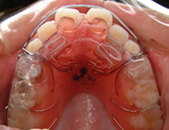

歯列矯正用咬合誘導装置(ムーシールド)は幼児期の早い段階で、反対咬合(受け口)を治す治療法です。装置はマウスピースみたいな透明の装置を、寝る時に装着します。月に1度のペースで装置を、調整していきます。

正面から観たところです。